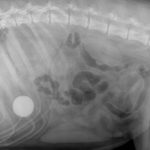

Yes, a dog can accidentally swallow a golf ball. The size of the ball poses a choking risk to canines. Dogs are naturally curious creatures, often using their mouths to explore the … [Read more...]